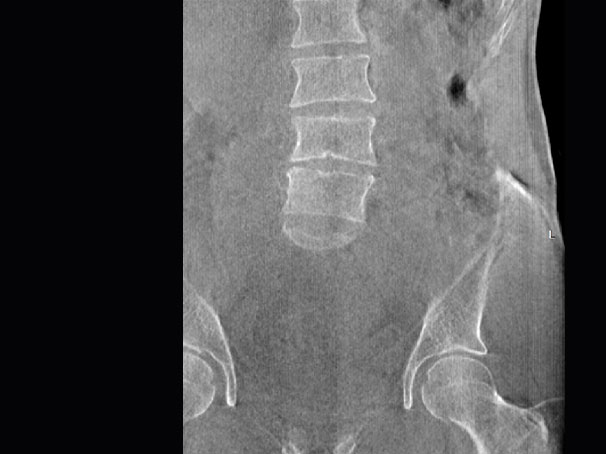

髋关节

腰椎

精准诊断

手术方案规划

术后随访